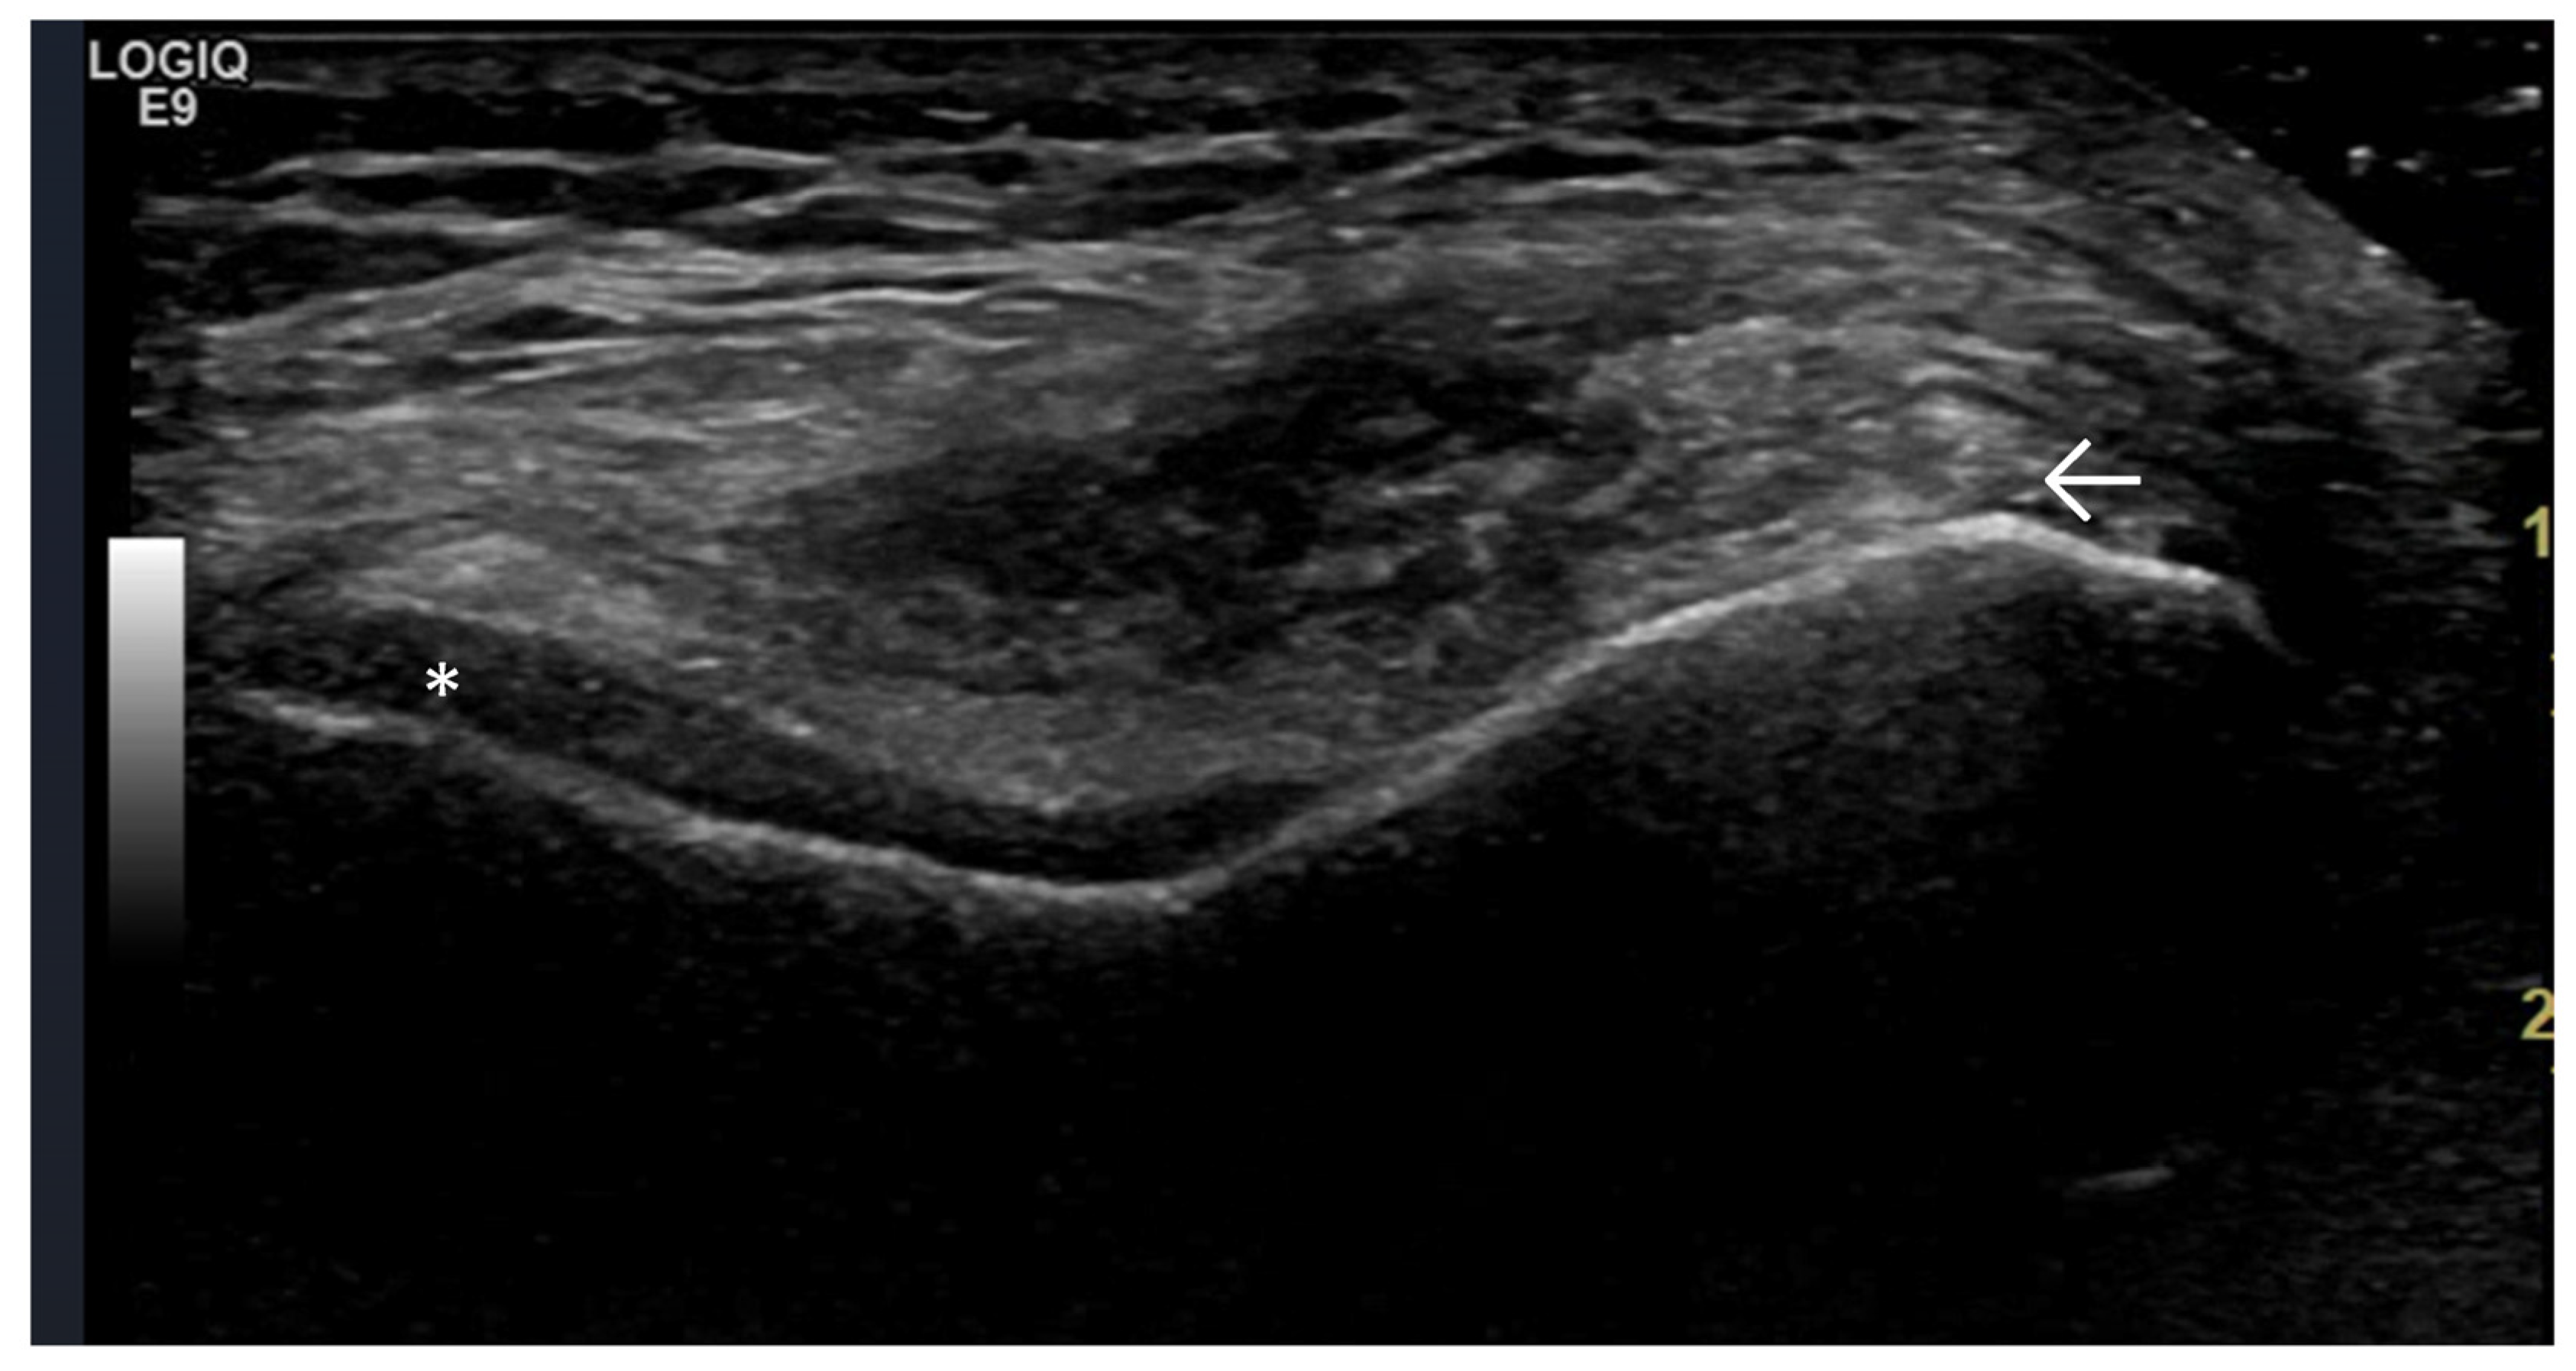

- Changes in extra-articular soft tissue (ligaments, tendons, capsule, entheses, muscles, bursae, Baker’s cysts, menisci—for knee joints); periarticular cystic lesions (including meniscal);

4. Examples of US Phenotypes